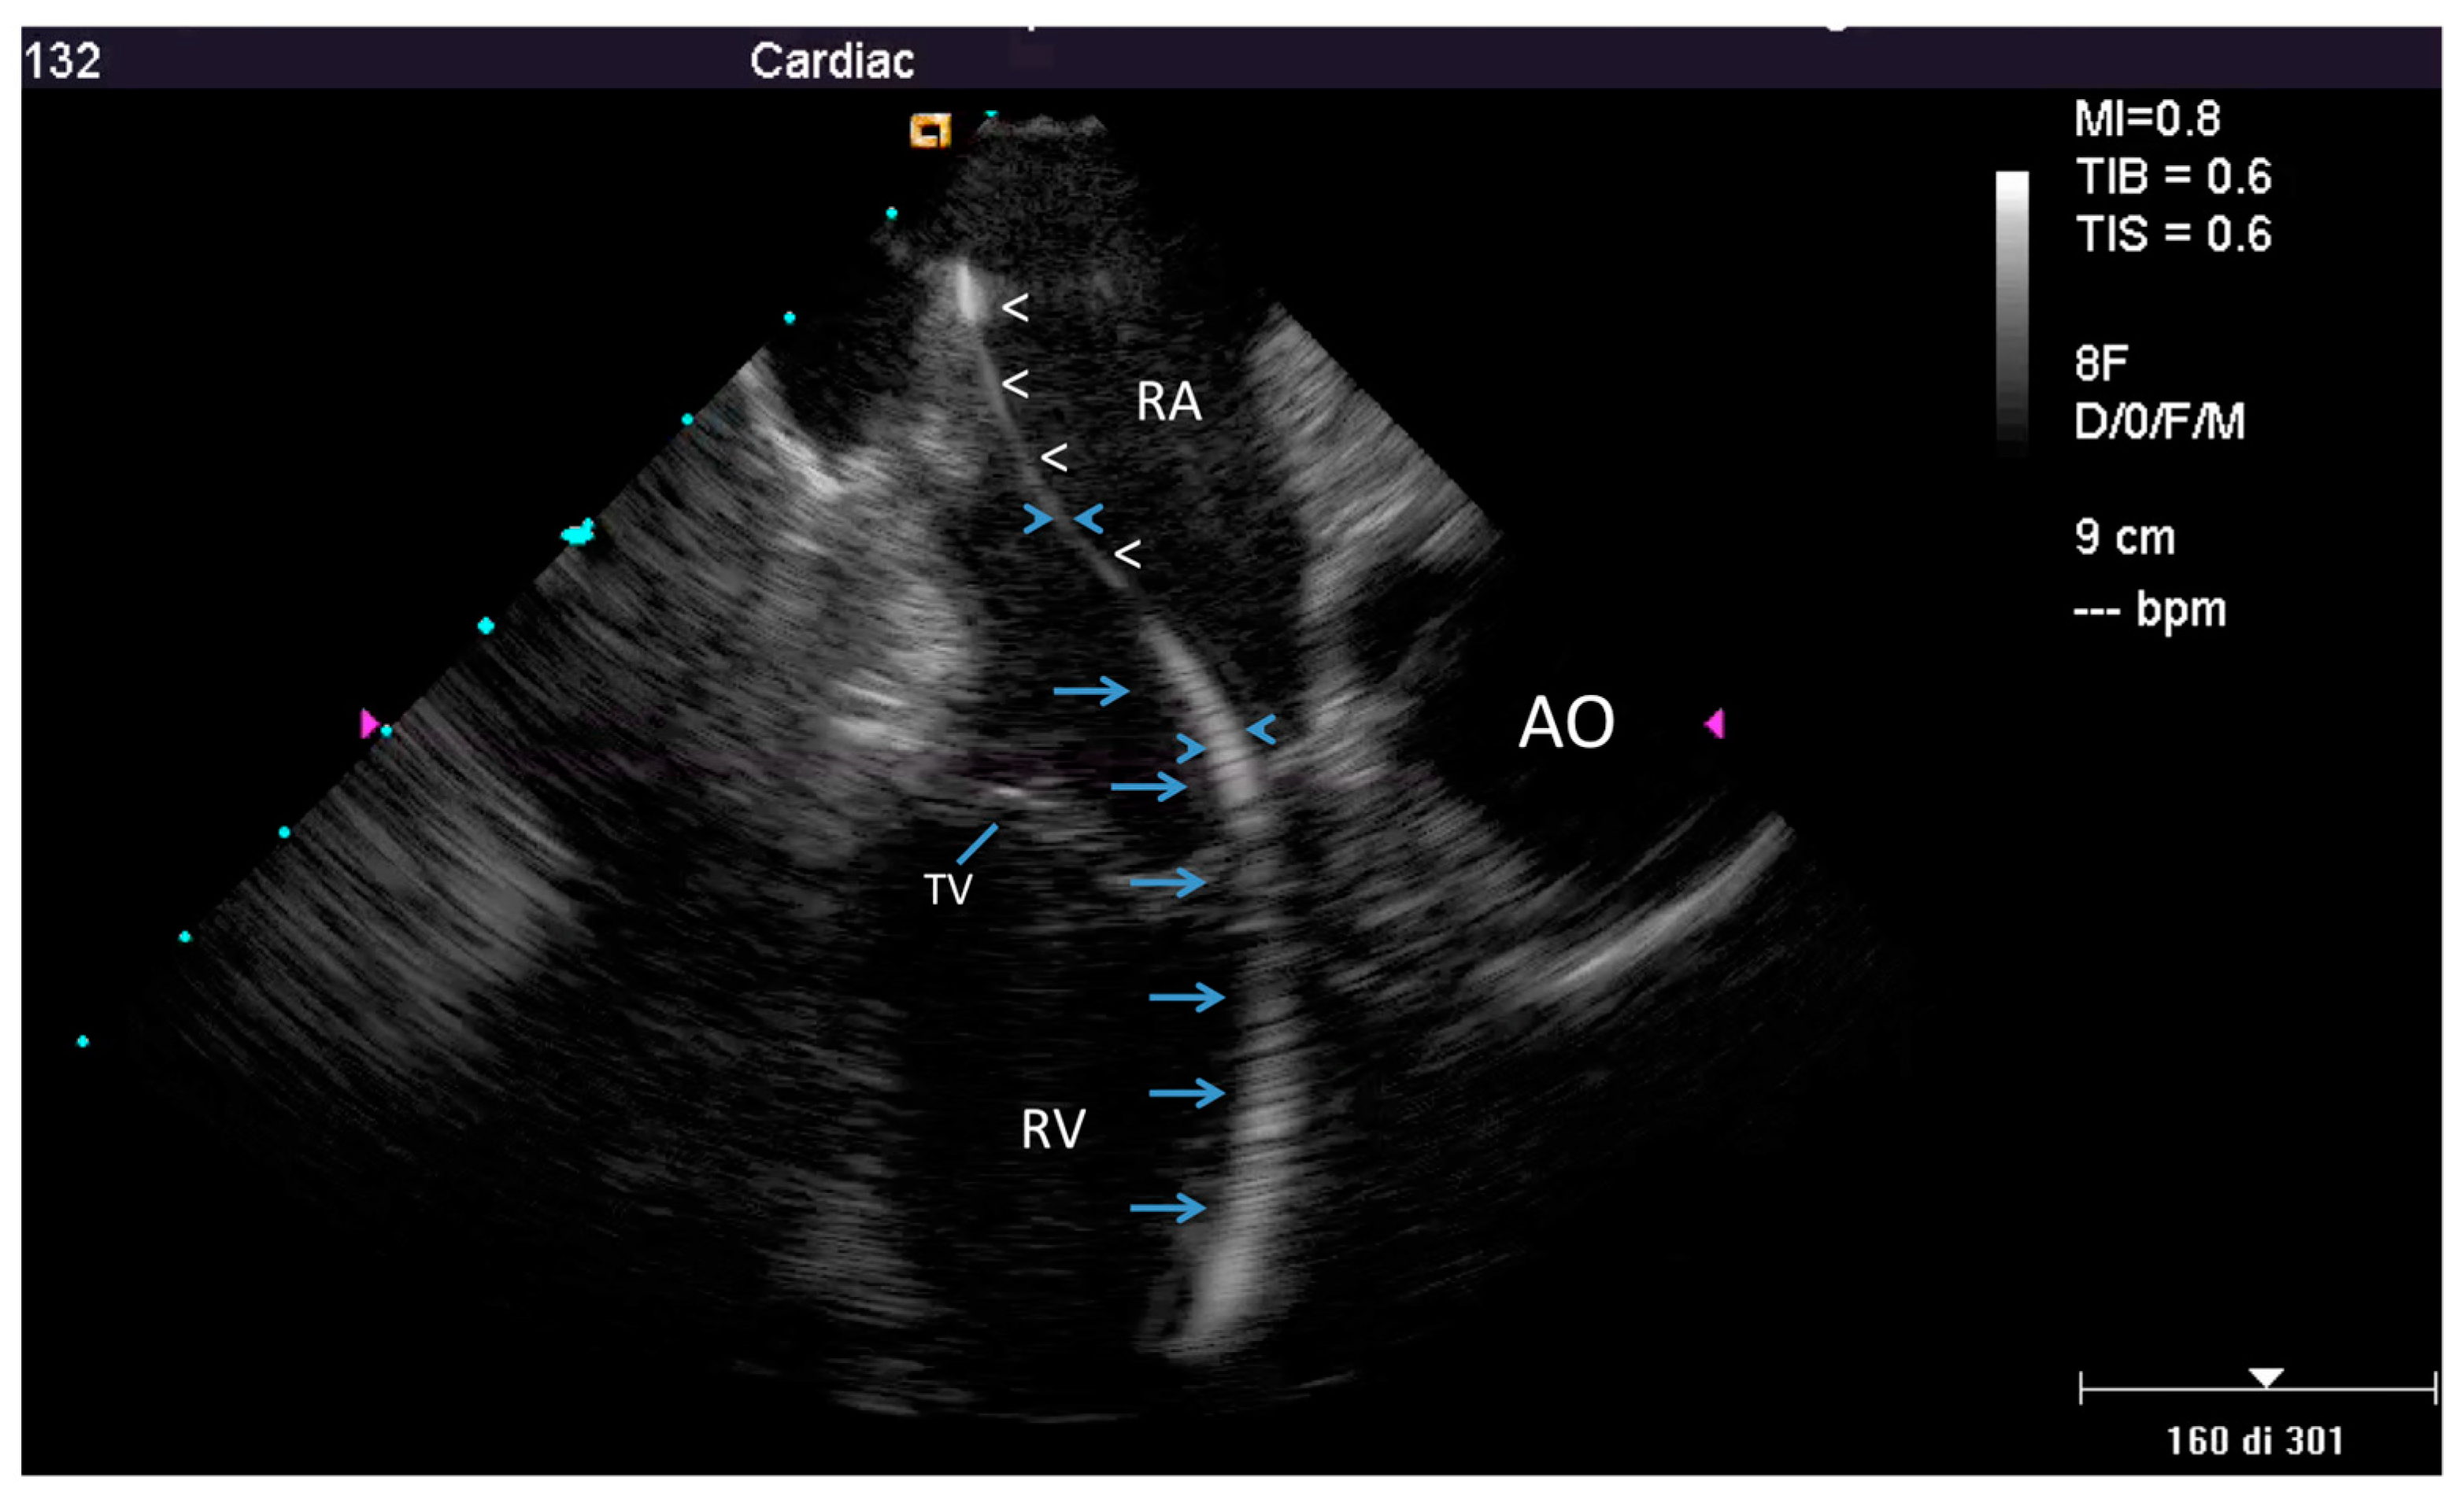

2.2.2. After the Extraction

3.2. Post-extraction ICE

4.2. Nature of the Ghost